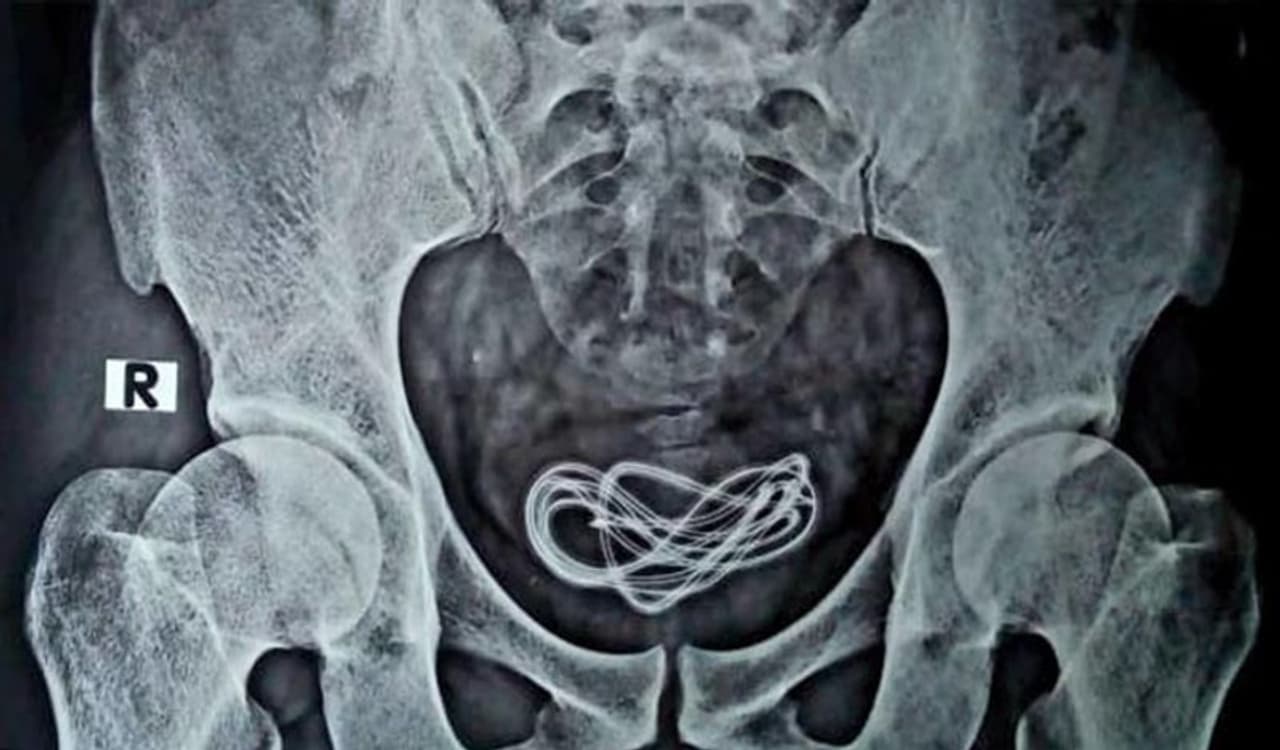

जब बच्चे की एक्सरे रिपोर्ट आई, तो सब हैरान रह गए। उन्होंने देखा कि बच्चे के ब्लेडर में दो फुट लंबी तार है। इसके तुरंत बाद बच्चे को एडमिट कर लिया गया।

डॉक्टर्स ने सर्जरी कर बच्चे के मूत्राशय से दो फुट की तार बाहर निकाली। जब बच्चे से इसके बारे में पूछा गया तो उसने बताया कि तीन महीने पहले उसने इस तार को प्राइवेट पार्ट के जरिये बॉडी में घुसाया था।

डॉक्टर्स ने सर्जरी के बाद बच्चे की जान बचा ली। उन्होंने कहा कि गनीमत है कि तार से बच्चे को कोई नुकसान नहीं पहुंचा। इस सर्जरी में घंटे का समय लगा। जिसके बाद 70 सेंटीमीटर लंबा तार बाहर निकाला गया।